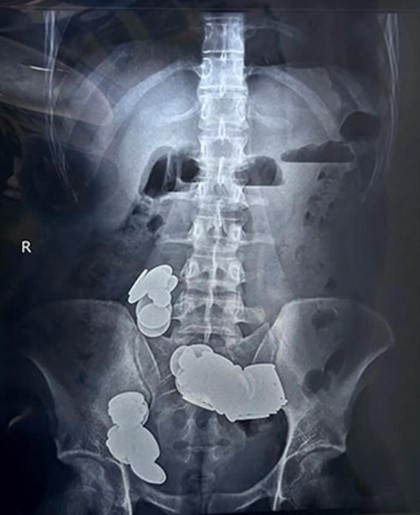

Médicos retiram 39 moedas e 37 ímãs do intestino de fisiculturista que os engoliu para ‘absorver zinco’

Um fisiculturista de 26 anos engoliu moedas e ímãs achando que os objetos ajudariam na musculação. O caso ocorreu na Índia.

Segundo a agência indiana de notícias ANI, médicos do hospital Sir Ganga Ram, em Nova Delhi, retiraram 39 moedas e 37 ímãs do intestino de um paciente. O jovem fisiculturista teria problemas ps1quiátricos e engoliu os materiais acreditando que eles liberariam zinco em seu organismo, o que, por consequência, melhoraria os efeitos da musculação.

O paciente chegou ao pronto-socorro com queixas de vômitos e dores abdominais há mais de 20 dias. Ele também não conseguia ingerir nenhum alimento.

Os familiares do jovem, citados pela agência, disseram que ele estava há semanas comendo moedas e ímãs e que vinha realizando tratamento ps1quiátrico. Os procedimentos cirúrgicos foram bem sucedidos e o paciente recebeu alta após sete dias.